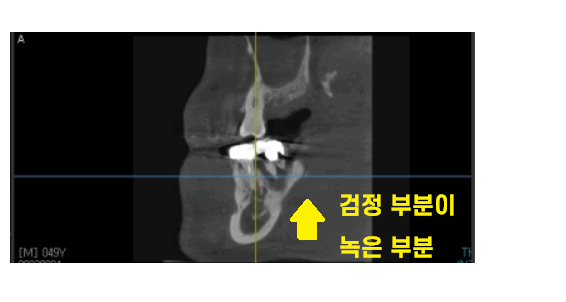

치아를 뽑기 전 ct 사진입니다.

치아 주변으로 검정색 웅덩이를 보실 수 있죠?

이게 다 뼈가 녹은 부분입니다.